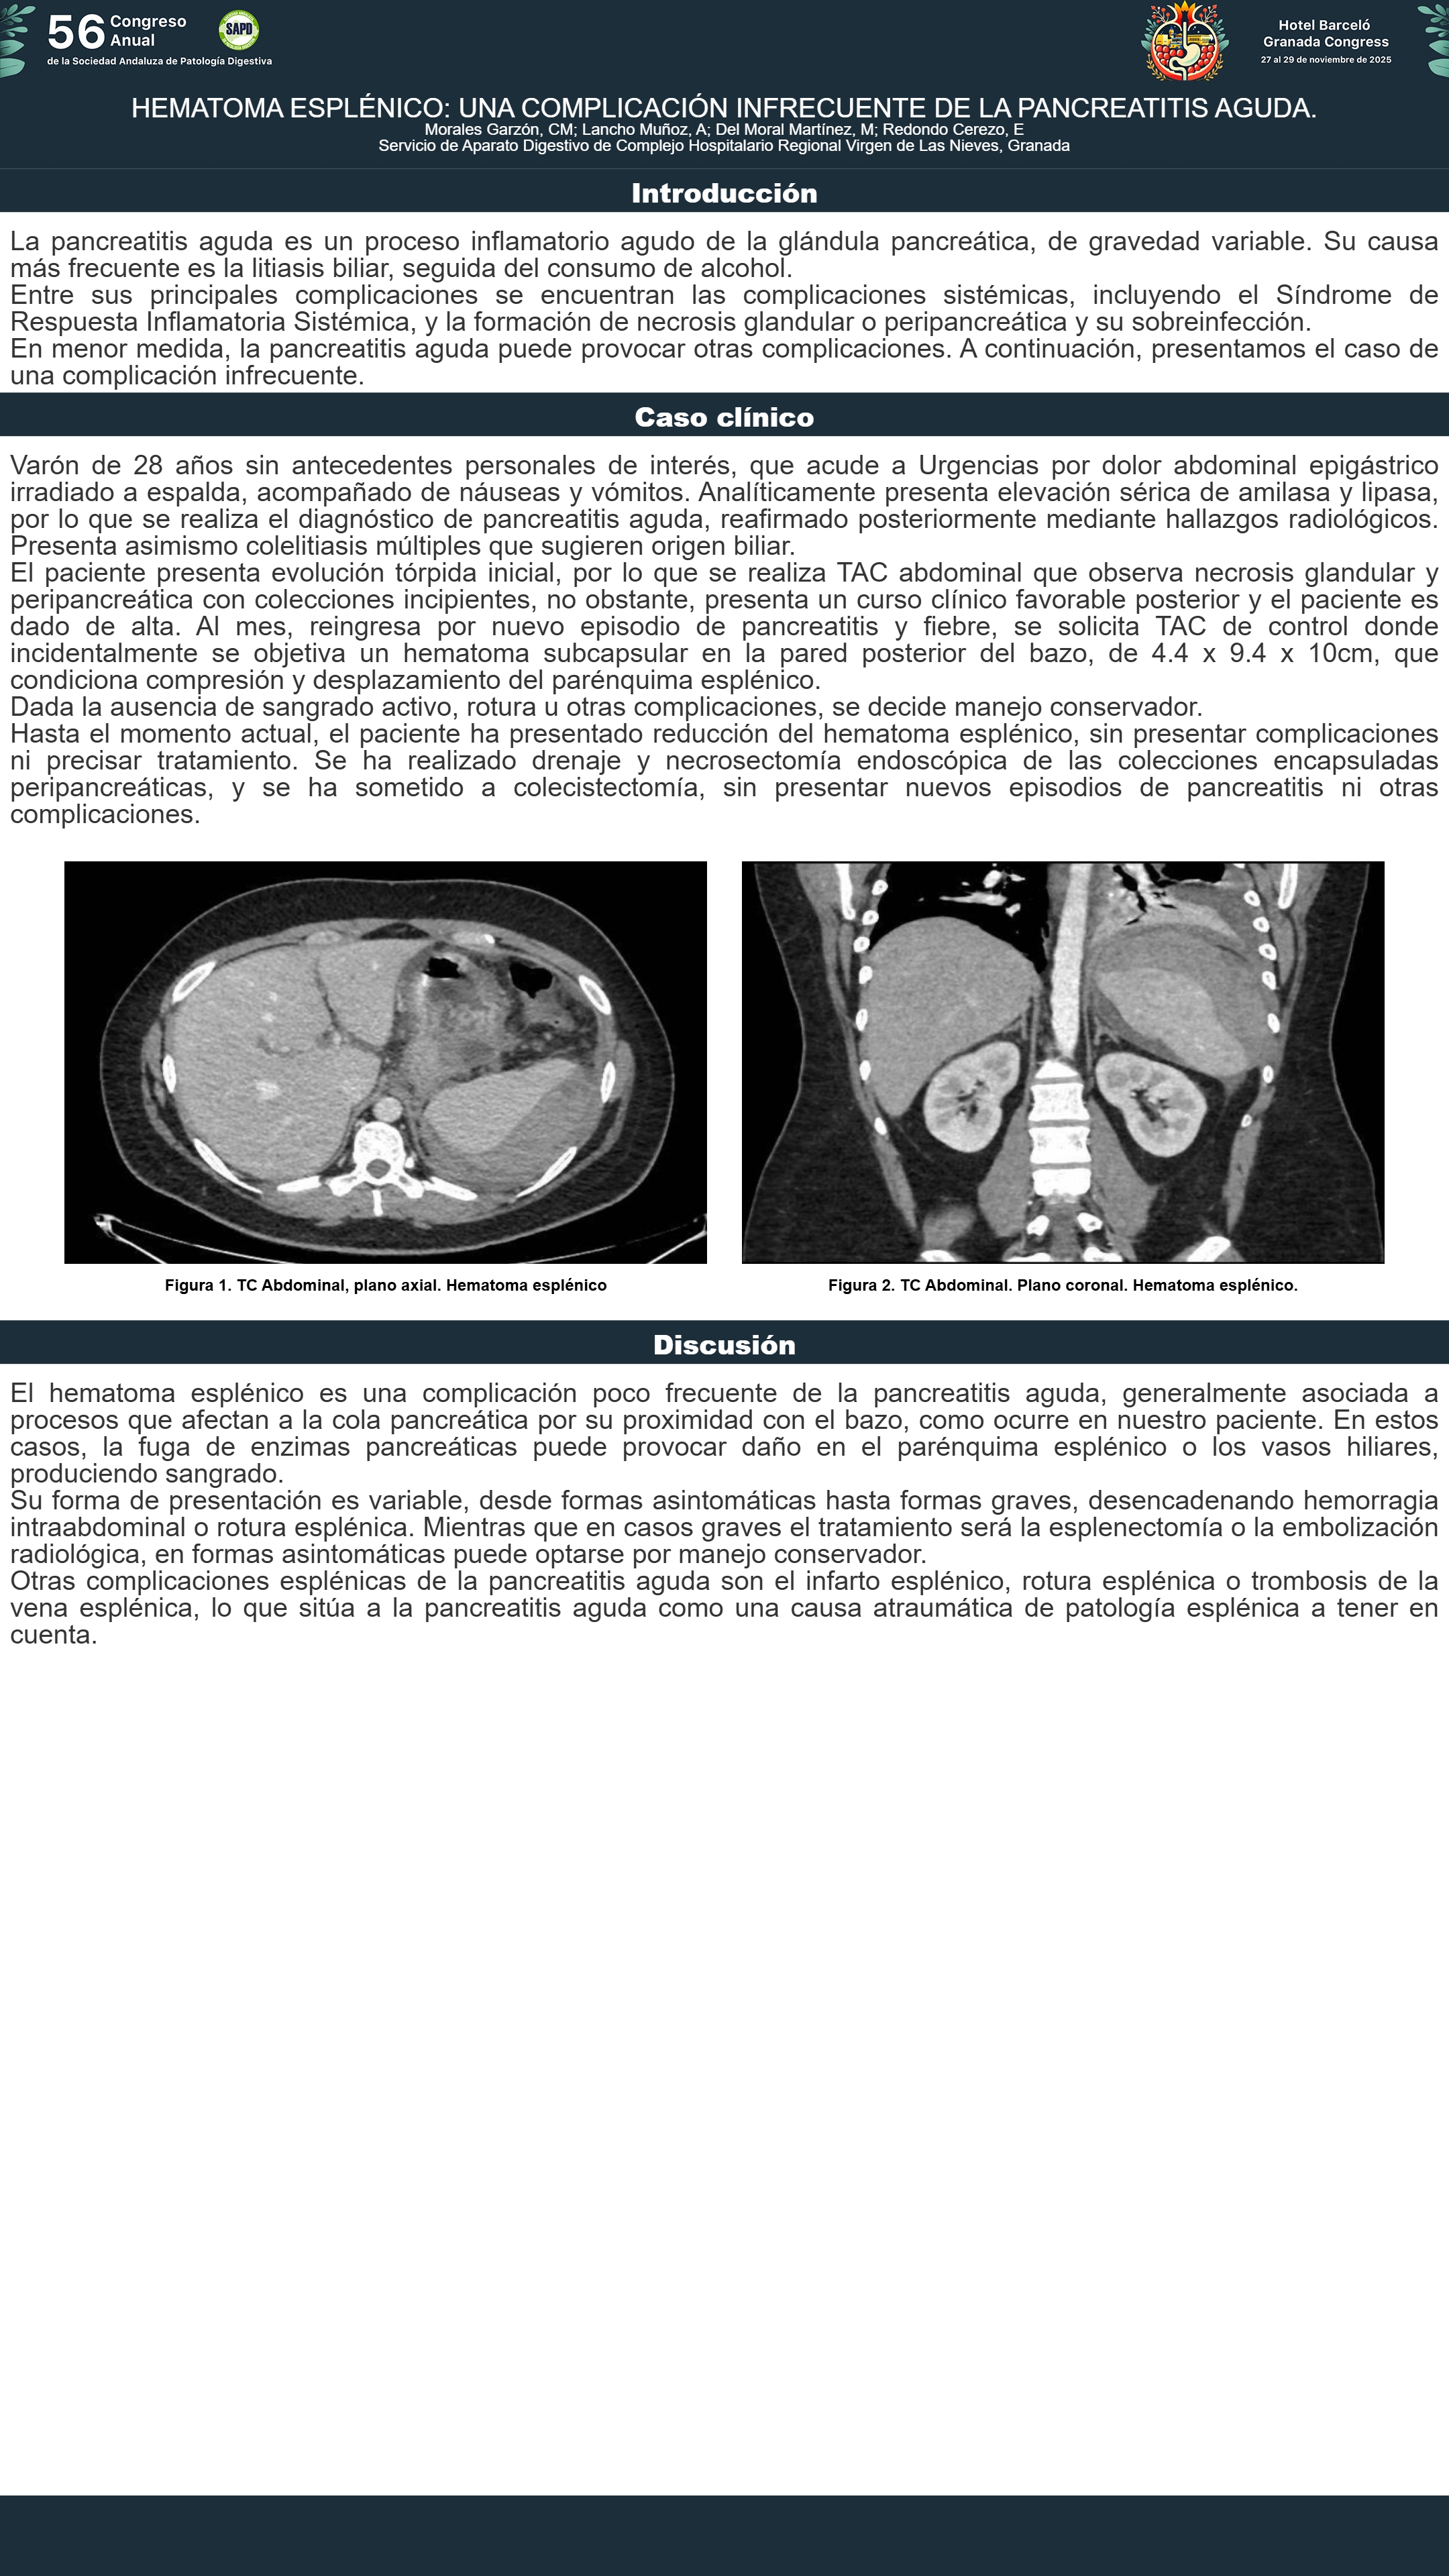

[CP-135] PANCREATITIS AGUDA Y SUS COMPLICACIONES: EL BAZO COMO PUNTO CRÍTICO